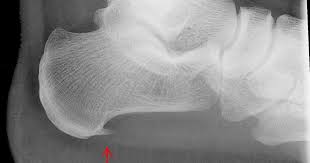

Pengapuran sendi atau osteoartritis ( osteoarthritis ). Jenis dan punca kepada masalah lutut berbunyi. Patang/retak tulang dibahagian lutut akan menjejaskan fungsi lutut serta mendatangkan kesan menyakitkan ketika menampung berat. Anda mencari punca penyebab lutut sakit di usia muda? Lutut berbunyi seperti meletup (krepitus) kerana geseran antara tulang pada permukaan kartilaj yang menyelaputi sendi tidak rata dan licin.

Anda hanya perlu membungkus segenggam es batu dengan handuk yang tipis. Tak sangka lutut acl dah okey sejak guna prokas! Lutut berbunyi seperti meletup (krepitus) kerana geseran antara tulang pada permukaan kartilaj yang menyelaputi sendi tidak rata dan licin. Hentakan kepada struktur bertulang yang boleh menyebabkan salah satu tulang di bahagian lutut pecah. Lutut sakit sering disertai dengan keluhan lutut terasa kaku, sulit diluruskan nyeri lutut biasanya terasa lebih hebat pada saat lutut digerakkan.